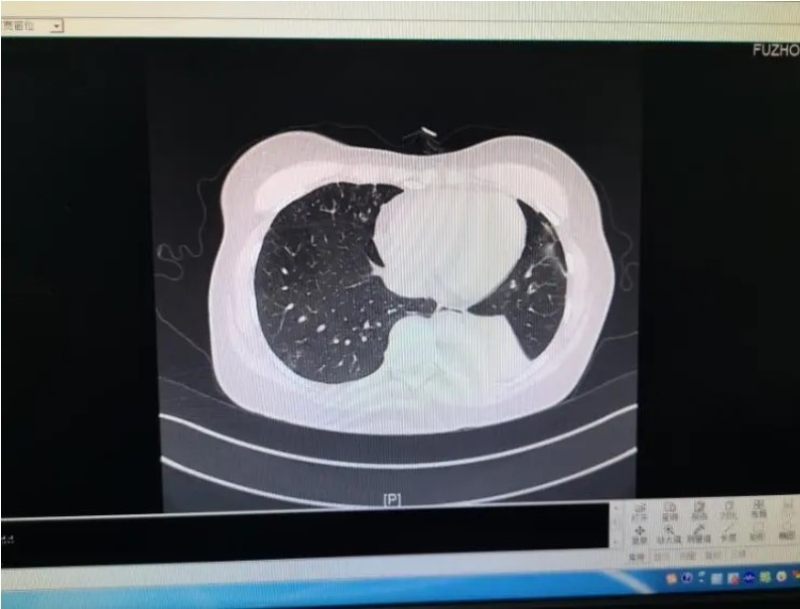

ความจริงแล้วโรคปอดบวมจากเชื้อราไม่ใช่เรื่องใหม่ ในปีที่ผ่านมา มีผู้ป่วยเข้ารับการรักษาในโรงพยาบาลแห่งหนึ่งในมณฑลฝูเจี้ยน หญิงคนดังกล่าวมีอาการไอมาเป็นเวลา 2 เดือนแล้ว และได้รับการวินิจฉัยว่าเป็นโรคแอสเปอร์จิลลัส (Aspergillus) ในหลอดลมปอดชนิดรุกราน แพทย์ทำการตรวจชิ้นเนื้อเนื้อตายและตรวจทางพยาธิวิทยา พบว่ามีเชื้อราจำนวนมาก